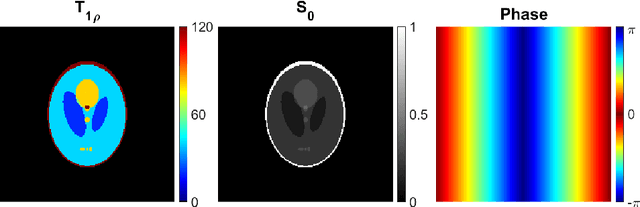

Abstract:Quantitative MRI (qMRI) methods allow reducing the subjectivity of clinical MRI by providing numerical values on which diagnostic assessment or predictions of tissue properties can be based. However, qMRI measurements typically take more time than anatomical imaging due to requiring multiple measurements with varying contrasts for, e.g., relaxation time mapping. To reduce the scanning time, undersampled data may be combined with compressed sensing reconstruction techniques. Typical CS reconstructions first reconstruct a complex-valued set of images corresponding to the varying contrasts, followed by a non-linear signal model fit to obtain the parameter maps. We propose a direct, embedded reconstruction method for T1rho mapping. The proposed method capitalizes on a known signal model to directly reconstruct the desired parameter map using a non-linear optimization model. The proposed reconstruction method also allows directly regularizing the parameter map of interest, and greatly reduces the number of unknowns in the reconstruction. We test the proposed model using a simulated radially sampled data from a 2D phantom and 2D cartesian ex vivo measurements of a mouse kidney specimen. We compare the embedded reconstruction model to two CS reconstruction models, and in the cartesian test case also iFFT. The proposed, embedded model outperformed the reference methods on both test cases, especially with higher acceleration factors.